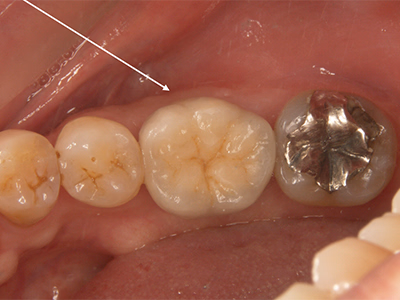

治療前後写真

治療前

治療後

右下の歯がぐらぐらして咬めない

治療内容

- ① 重度歯周病のため抜歯 → 治癒後プランニング

- ② 1次手術時に骨造成を併用してインプラント埋入

- ③ 3ヶ月後、2次手術時に歯肉移植(歯肉補強術)を併用

- ④ 最終補綴装着後、メンテナンスへ移行

医院コメント

骨造成と歯肉補強を段階的に行い、清掃性・耐久性の高い周囲組織を再建。

埋入から15年経過時点でも良好に機能。